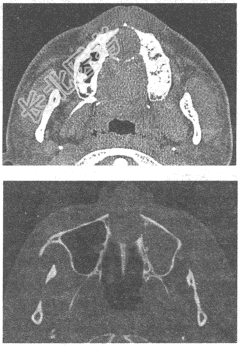

- 单项选择题女性,21岁, 上切牙后方发现一囊性突起1年,无明显疼痛。CT表现如下图所示, 最可能的诊断为

A、上颌骨含牙囊肿

B、上颌骨造釉细胞瘤

C、牙根囊肿并感染

D、腭正中囊肿

E、始基囊肿